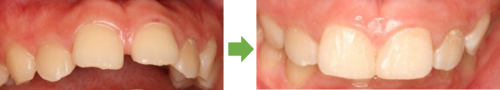

術前

下両奥歯 被せ物装着後